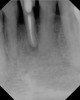

Figure 9  Clinical case of invasive cervical resorption that was deemed nonrestorable and the tooth removed.

Figure 9

Figure 10  Clinical case of idiopathic resorption of the upper second bicuspid. The tooth was deemed hopeless and extracted.

Figure 10